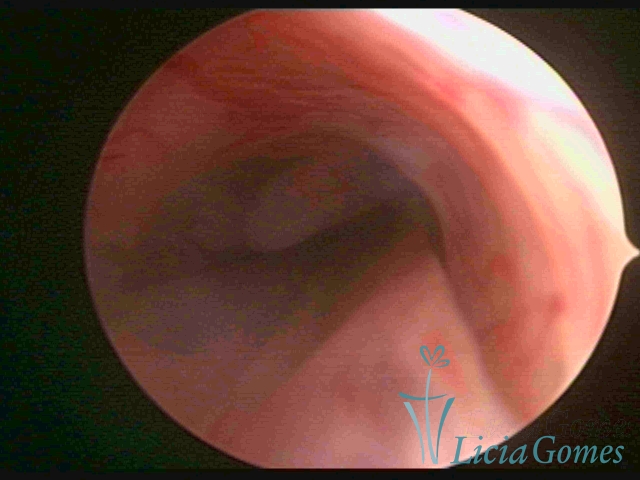

ENDOCERVICAL POLYPS

Benign tumors resulting from the reactive focal proliferation to inflammatory processes or hyperestrogenism situations, which may be sessile (with a large implantation) or stalked.